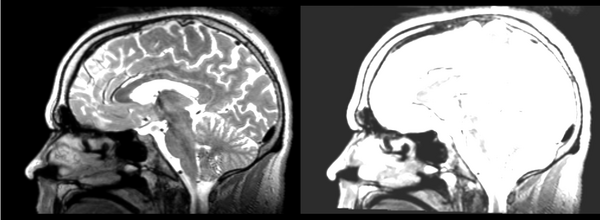

Affine

01053>01031_affine.png = looks good in terms of size. odd warping of frontal lobe and cerebellum area, but otherwise good coregistration.

B-spline

01053>01031_bspline.png = looks good in terms of size. odd warping of frontal/temporal lobe and cerebellum area, but otherwise good coregistration.

Diffeomorphic Demons

01053>01031_demons.png = 10 minutes. Window/leveling initially off. Otherwise, it looks really good. Not much distortion.